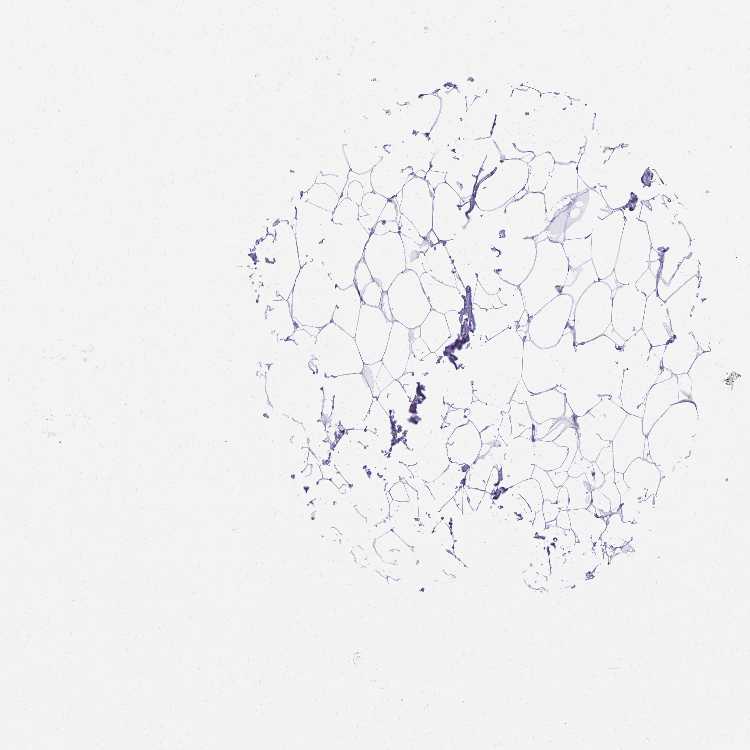

BREAST - Antibody stainingi

Antibody staining in the annotated cell types in the current human tissue is reported as not detected, low, medium, or high, based on conventional immunohistochemistry profiling in selected tissues. This score is based on the combination of the staining intensity and fraction of stained cells.

Each image is clickable and will lead to virtual microscopy that enables deeper exploration of all samples and also displays staining intensity scores, fraction scores and subcellular localization as well as patient and tissue information for each sample.

Antibody HPA058287

Adipocytes Not detected

Glandular cells Not detected

Myoepithelial cells Not detected